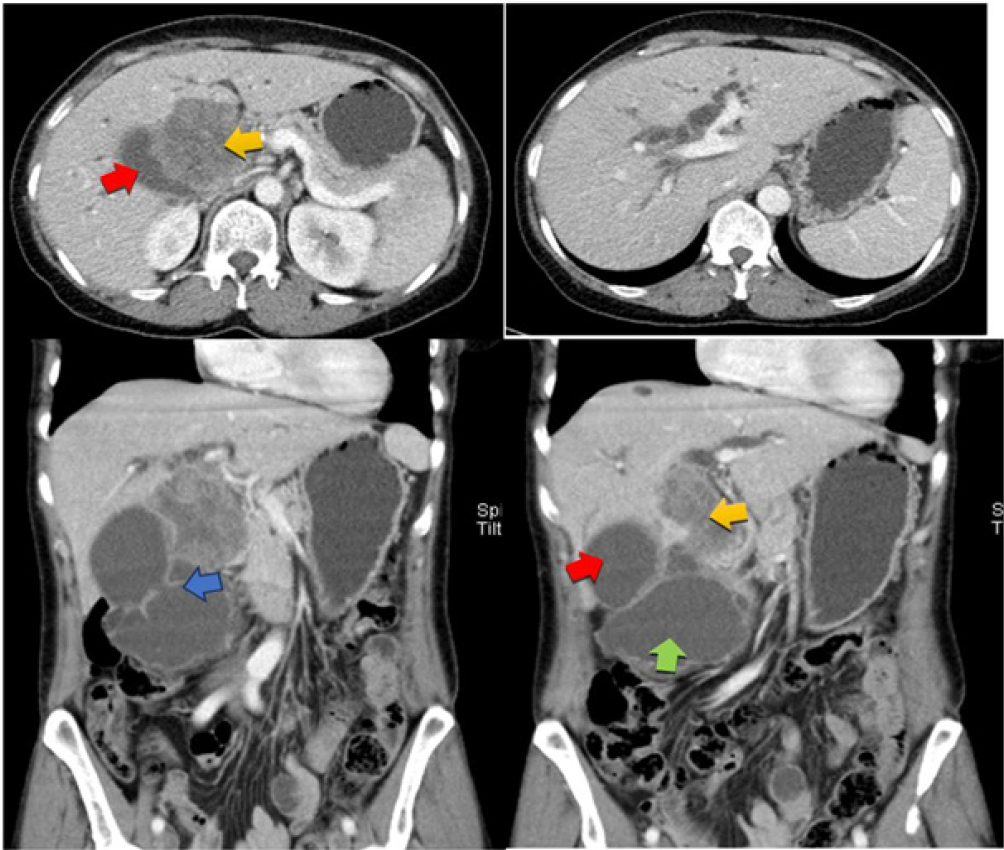

Introduction: Gallbladder carcinoma is a malignant epithelial neoplasm of the gallbladder. The tumor is clinically aggressive, with an overall 5-year survival rate of < 10%. Cholelithiasis is a known and established risk factor. Up to 50% of gallbladder tumors are detected incidentally in routine cholecystectomy specimens due to the absence of gross abnormalities. Gallbladder carcinoma has several unusual presentations, one of which is an incidental pseudocyst with cholelithiasis and perforation. This unusual occurrence makes the index case unique.

Case presentation: We report a case of gallbladder cancer diagnosed by an emergency cholecystectomy, performed for acute cholecystitis caused by a pseudocyst. The patient underwent chemotherapy, and currently, 12 months have passed. The patient is doing well, without signs of recurrence or metastasis.